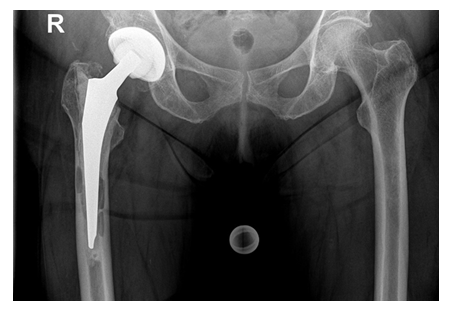

The primary surgical procedure was a THA in 17 cases and a hemiarthroplasty in five cases (Figure 8).

Intraoperatively, the beads could be completely removed through an endofemoral approach without having any difficulties. Based on the bone quality, presence of any osseous defects and occurrence of fractures, a cementless modular straight stem (Restoration® , Fa. Stryker, Duisburg, Germany) was used in 14 cases and a cemented proximal femur replacement stem (GMRS®, Fa. Stryker, Duisburg, Germany) in four cases, respectively. In the latter cases, the bone defects and the non-intact femoral isthmus would not have provided for a sufficient cementless fixation, therefore cemented implants were solely chosen. In all cases, Palacos R+G® (Fa. Heraeus Medical, Bad Homburg, Germany) was used. The abductor muscles were fixated onto the prosthesis through the fixation holes with non-absorbable sutures (Ethibond Excel 2-0, Fa. Ethicon). For the acetabulum, a press-fit cup (Tritanium®, Fa. Stryker, Duisburg, Germany) and an antiprotrusio cage combined with a cemented cup (Burch-Schneider cage, Fa. ZimmerBiomet, Freiburg i. Br., Germany) were implanted in eight cases, respectively, whereas a bipolar head (UHR®, Fa. Stryker, Duisburg, Germany) and a cemented constrained liner (Trident®, Fa. Stryker, Duisburg, Germany) were used in one case, respectively. Suction drains were routinely placed in all cases. The mean surgery time of the second stage was 162 [84-319] minutes. Depending on the osteotomy length, the total length of the Restoration® stems used varied between 225 and 295mm (9x 155mm, 5x 195mm with various length of cone bodies) (Figure 9). Postoperatively, all patients were allowed to put full weight-bearing onto the operated leg.

At a mean follow-up of 43 [24-85] months 16/17 (94%) of the cases that underwent prosthesis reimplantation were free of any local or systemic infection signs. There was no case of a stem subsidence. All osteotomies showed a complete osseous consolidation after three to six months (Figure 9).